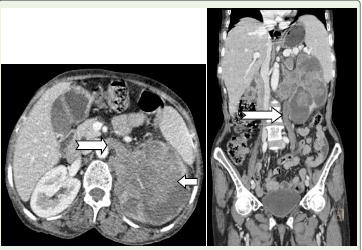

Routine blood investigations were performed and reports were available. Contrast-enhanced CT of the abdomen and pelvis revealed a large hypodense, hypoenhancing mass arising from the left renal pelvis, measuring approximately 7.4 × 7.2 cm in axial dimension and 9.8 cm in craniocaudal extent [Figure 1]. The lesion caused severe pelvicalyceal dilatation with marked thinning of renal parenchyma. Frond-like intraluminal extensions into the calyceal system were noted. Tumoral encasement of the left renal artery and extension into the left renal vein were present.

The mass showed extension into the proximal and mid left ureter with resultant dilatation, while the distal ureter appeared normal. An additional lesion was noted at the left vesicoureteric junction, producing a filling defect within the urinary bladder [Figure 2]. Enlarged left renal hilar lymph nodes were identified. Associated findings included mild hepatomegaly with multiple hypodense lesions suggestive of metastases [Figure 3] and splenomegaly.

Figure 1:CT venous phase of axial and coronal image shows: A large

hypodense hypoenhancing mass is seen in the left kidney with its epicenter

in the renal pelvis (long arrow) causing severe dilatation of the pelvicalyceal

sytem with thinned renal parenchyma (curvilinear black arrow) and showing

a frond like extension into the calyceal system. Tumoral extension into the

left renal vein is seen (short wide arrow). Lymph node posterior to the left

renal vein (Thin black arrow).

Tumoral extension into the left proximal and mid ureter is seen in the coronal

image which is dilated (white arrow).